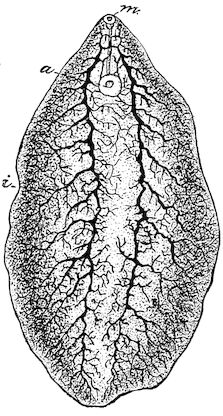

Fig. 9.—C, horn; P, modified skin forming the keratogenous membrane; O, horn core, exhibiting a double sinus.

(2.) The horn-secreting membrane is formed by the skin, which undergoes special development around the base of the horn and comes to resemble that of the coronary band, from which the hoof or claw is secreted. The band is about one-fifth of an inch in breadth. The papillæ of the dermis are specially developed at this point, and the epithelium which they secrete eventually forms the horn.

The internal surface of the growing horn is adherent to the horn core through the medium of another tissue formed by a specially differentiated periosteum which is continuous with the periosteum covering the frontal bone. It is not a true periosteum, but a vascular tissue formed of papillary layers analogous to those of the podophyllous tissue of the ox’s claw or horse’s hoof.

This keratogenous membrane receives a rich vascular supply from the arterial circle formed at the base of the horn core by a division of the external carotid, the blood conveyed by which is freely distributed to the enlarged papillæ. The great vascularity of these parts 23explains why lesions of the horns are often followed by such profuse bleeding.

(3.) The horn secreted by the papillæ of the horn band (which is analogous to that of the coronary band of the horse) forms a cone varying in its curve in various breeds. Its base is hollow, and contains little depressions holding the papillæ from which the horn is secreted. From its base up to the end of the horn core the walls progressively increase in thickness. From this point it is solid; in a fully-grown horn the bone does not extend more than one-half or two-thirds of the entire length.